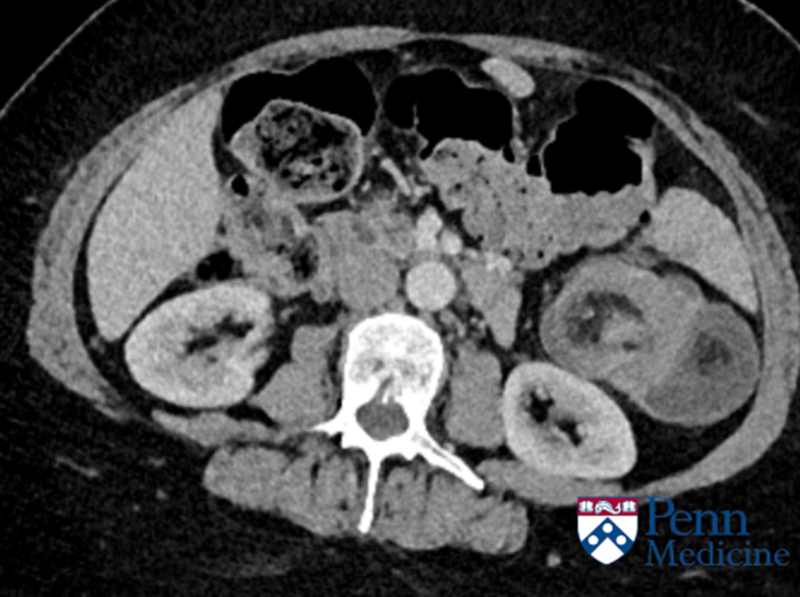

55-year-old man with abdominal pain

A 55-year-old man presented with abdominal pain.